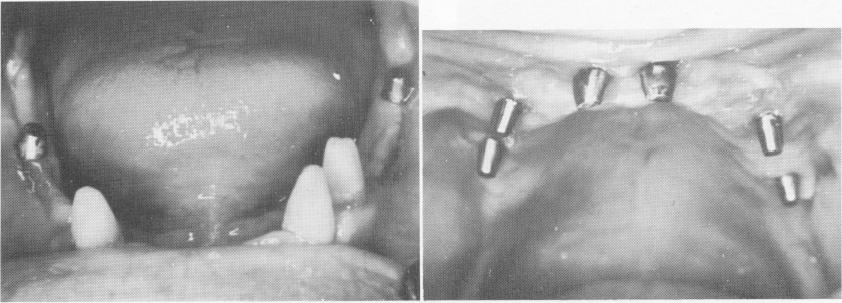

Fig. 11-159. Preoperative view of patient's existing teeth and prosthesis.

Fig. 11-160. Blade implants were placed in the edentulous maxilla and sutured.

Fig. 11-161. When the tissues had healed, impressions were taken for the prostheses.

1 Preoperative view of patient`s existing teeth and prosthesis

2 Blade implants placed in edentulous maxilla and sutured

3 After upper & lower arch tissues healed, impressions taken for prostheses